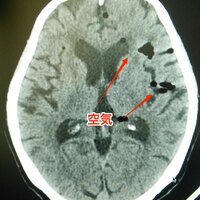

タップテスト(髄液排除試験)後に頭痛の訴えあり。何が起きたのか?

タップテスト(髄液排除試験)とは? タップテストとは、腰椎穿刺(腰椎の隙間から針を差し込む検査)を行い、脳脊髄液を採取する検査のことである。 髄膜炎や神経変性疾患が疑われる場合に行われるが、正常圧水頭症が疑われる場合には、脳脊髄液を抜いて症状が改善するかを観察する。 脳神経外科や神経内科領域においては、最…